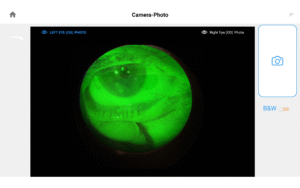

Pushing ahead, our imaging system includes our new, patent-pending Halo background light. Working with native slit lamp illumination, Halo delivers unparalleled clarity of the ocular adnexa. You’ll uncover details of the meibomian glands, acinar spaces, conjunctiva, lid margins, and lashes like never before.